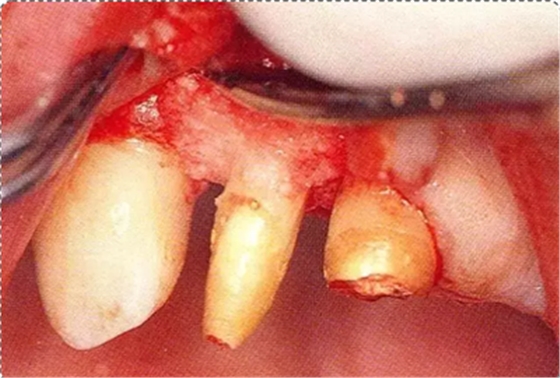

圖10-3 考慮到審美性,應(yīng)用牙齦乳頭保存術(shù)(Papilla preservation technique),進行了自體骨移植。

圖10-4 骨缺損部位進行骨修整結(jié)束的狀態(tài)。